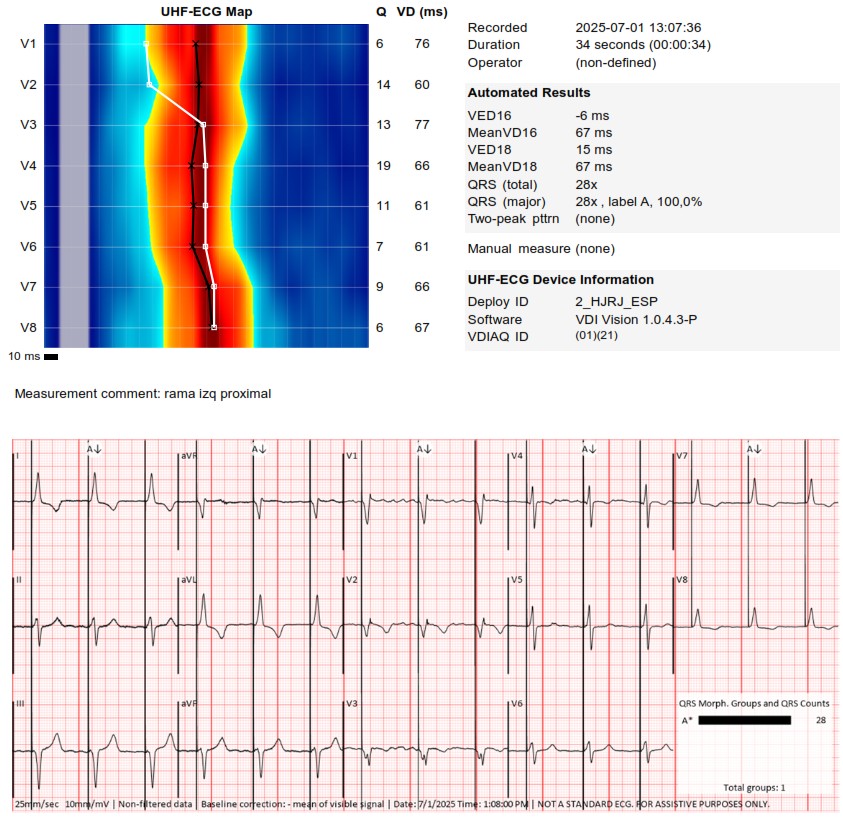

I strongly support HBP, but in this case,the great improvement in QRS didn't correct the asynchrony measured with UHF ECG.We opted for LBBAP despite the RV delay.The final programming AV 70 ms and fusion with native rhythm achieved the best result with UHF ECG(very useful tool)

An interesting case was shared today. UHF-ECG can help to enhance the decision-making in less textbook-type cases.

These are UHF maps of the two patterns. The second one is a little bit deeper into the septum,